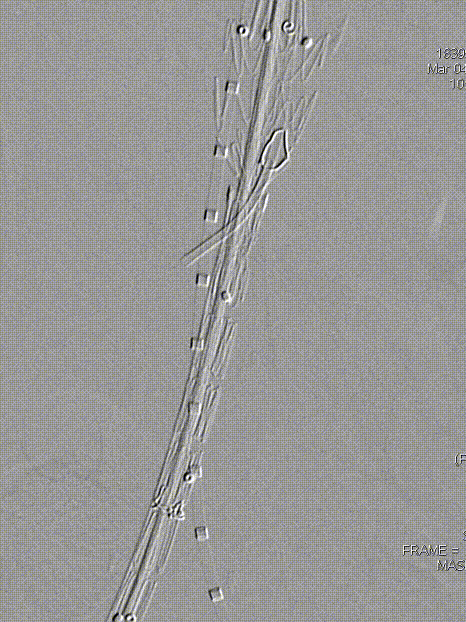

术前影像学诊断结果:腹主动脉穿通性溃疡伴假性动脉瘤形成。

腹主动脉末端壁间血肿伴局部穿通性溃疡,肠系膜下动脉粗大。